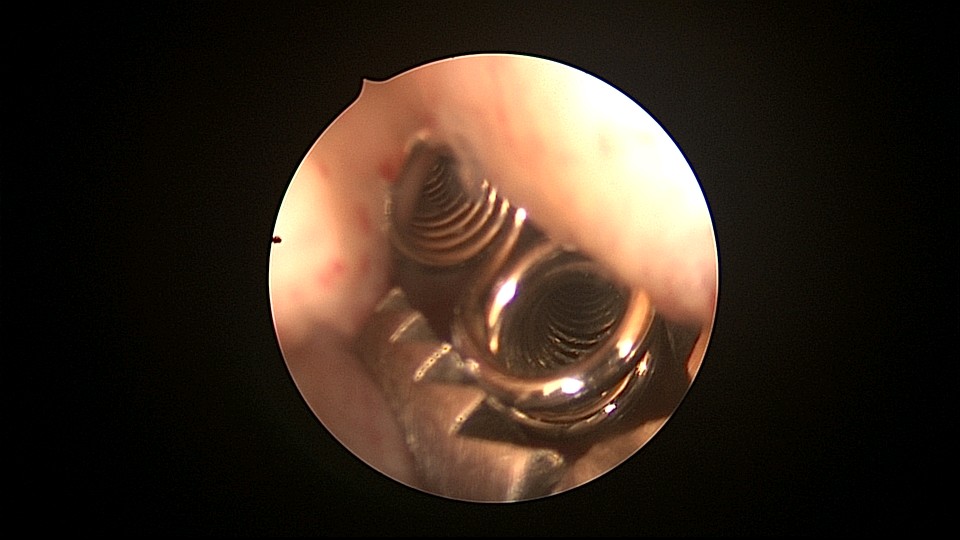

患者81岁,G5P5,顺产5次,安环50年,绝经23年,高血压病史多年,10年前因颅内肿瘤行开颅手术,4年前行腹腔镜胆囊切除术,外院介绍到我院宫腔镜取环。子宫前位,宫颈萎缩,穹隆展平,宫颈外口位于穹隆偏左侧,平滑狭小,夹持宫颈很困难,阴道内镜方式进入宫腔,见宫腔下部O型环圈内前后壁粘连,顿性分离粘连,宫腔中上部O型环与两侧宫壁嵌顿,异物钳松动节育环,但难以取出,取环钩沿镜鞘外侧进入宫腔,配合中弯钳牵拉出节育环,环变形,检查环完整,宫腔无其他异常。